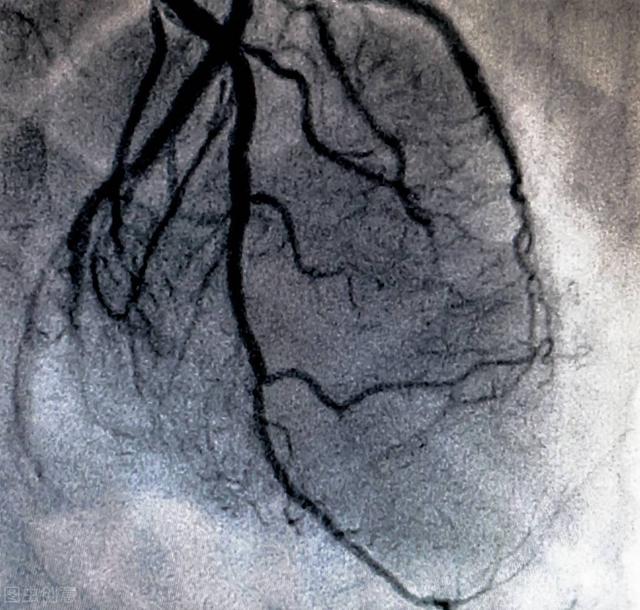

冠動脈造影は、冠動脈アテローム性動脈硬化性心疾患を診断する最も一般的な方法の一つであり、しばしば "冠動脈性心疾患 "と呼ばれる。また、冠動脈性心疾患を確認・診断するための "ゴールドスタンダード "でもある。

(2) 冠動脈性心疾患の診断:経験豊富な心臓血管系の医師にとって、上記の方法による冠動脈疾患の診断は10回中9回は正確である。冠動脈造影検査は冠動脈の閉塞をはっきり見ることができるので、冠動脈疾患を診断するためのゴールドスタンダードである。もちろん、一部の患者には冠動脈CTAを代替手段として用いることもできる。

現在。95%以上の患者が手首の橈骨動脈から行っている。医師は、橈骨動脈から冠動脈の開口部にホースを挿入して心臓の冠動脈の開口部に送り、造影剤を開いてX線を照射することで、心臓の血管が鮮明に見えるようにし、医師はその画像の展開を観察することで、心臓の動脈が狭窄しているかどうか、詰まっているかどうか、詰まっている場合はどの程度詰まっているのかを判断することができる。そこから冠動脈疾患なのか、他の心臓病なのかを判断することができる!